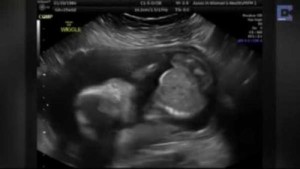

EE.UU.- “Yo le llevo dentro, pero es ella quien le protege”, afirma Brittani McIntire tras ver la ecografía que confirma que sólo uno de sus mellizos sobrevivirá. La familia se consuela pensando que aunque uno de sus bebés probablemente morirá antes de nacer, aunque afirma “pase lo que pase, no van a estar solos”.

La imagen de los hermanos cogidos de la mano ha conmovido a los padres de los pequeños. Uno de ellos es probable que no llegue a nacer, pero la unión entre ellos ya es evidente.

“Sabemos que una parte de ellos permanecerá unida para siempre y eso es algo muy especial”, añade Ian McIntire. “No se ve demasiado bien, pero se puede apreciar una mano diminuta cogiendo la de su hermana melliza” aclara emocionado.

El emotivo momento de los mellizos cogiéndose la mano será una imagen que la familia McIntire atesore durante toda la vida.